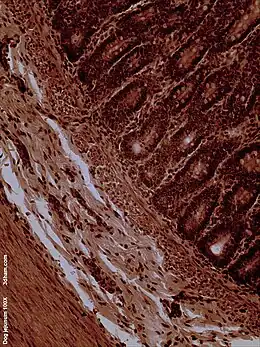

La superficie interna del yeyuno, formada por una membrana mucosa, está cubierta en las proyecciones llamadas vellosidades, que aumentan la superficie de tejidos disponibles para absorber los nutrientes de los alimentos previamente digeridos por el estómago. Las células anales epiteliales que recubren estas vellosidades tienen un número aún mayor de microvellosidades. Son las vellosidades y las microvellosidades las que permiten que en una pequeña porción de tubo digestivo, se absorba una gran cantidad de nutrientes. El transporte de nutrientes a través de las células epiteliales a través del yeyuno y el íleon incluye el transporte pasivo de la fructosa, el azúcar y el transporte activo de aminoácidos, péptidos pequeños, vitaminas, y la mayoría de la glucosa. El ácido fólico, metabolito esencial del ciclo celular, es absorbido principalmente a este nivel del intestino delgado. Las vellosidades en el yeyuno son mucho más largas que en el duodeno o el íleon.

Microscopía electrónica del yeyuno

ME del yeyuno de un ratón x14000